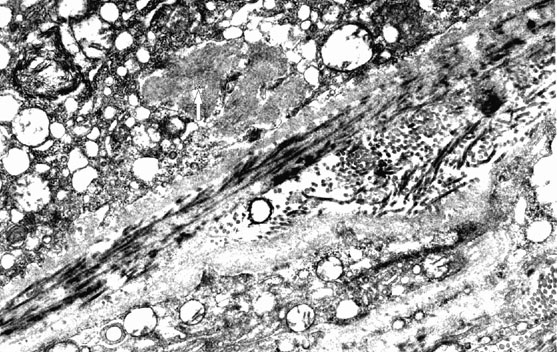

Figure 9. Sub-retinal pigment epithelial deposits in a mouse model of protoporphyria

Protoporphyric mouse model exposed to blue light demonstrates sub-retinal pigment epithelium fibrillogranular deposit (white arrow) with fibrils measuring up to 16 nm with a periodicity of 13 nm.